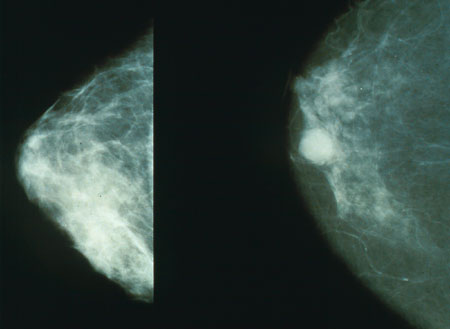

Questo studio, pubblicato sulla versione online di BMC Medical Genetics, si pone come uno dei primi a esaminare la possibile correlazione tra la grandezza del seno e il rischio di cancro. Altri precedenti studi e le conoscenze mediche si sono basate fino a oggi su altri parametri di valutazione, riferiti alla morfologia del seno, quali per esempio la densità della mammella. Se questi fattori sono più o meno noti, il rapporto tra la dimensione del seno e il tumore è invece poco chiaro. Questo studio ha pertanto cercato di fare un po’ di luce.